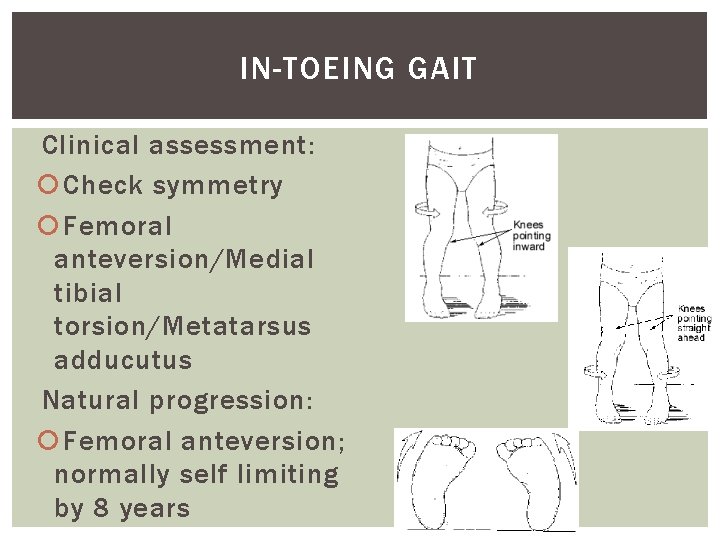

IN-TOEING GAIT Clinical assessment: Check symmetry Femoral anteversion/Medial tibial torsion/Metatarsus adducutus Natural progression: Femoral anteversion; normally self limiting by 8 years